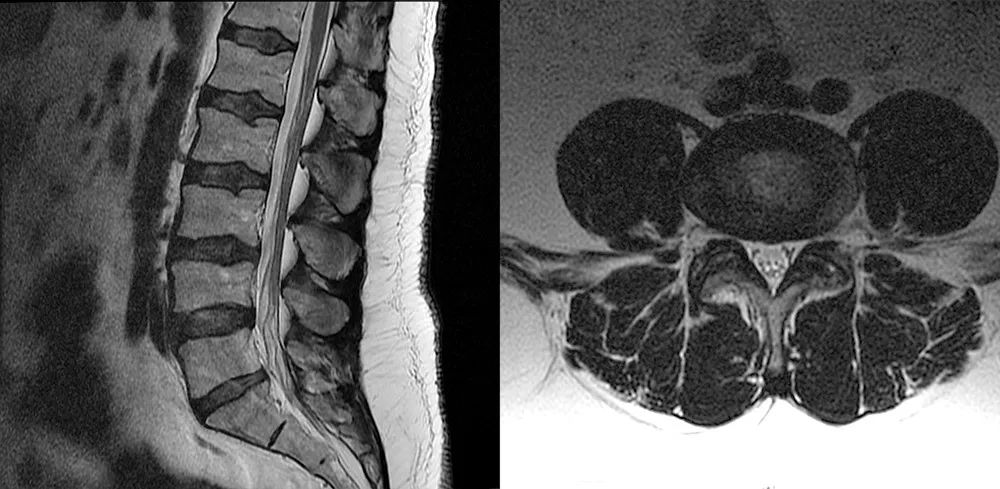

病例一

男,45 岁,1 年前出现慢性腰痛、双侧大腿麻木和无力感。临床查体无神经功能缺损。

本次腰椎 MR 检查:你发现了什么?

4.5 年前腰椎 MR 检查

4.5 年前和现在的腰椎 MR T2WI 轴位对比:L4-L5 水平,现在的 MR 发现马尾神经位置前移,更加聚拢;而 4.5 年前的 MR 发现马尾神经位置靠后,分散。